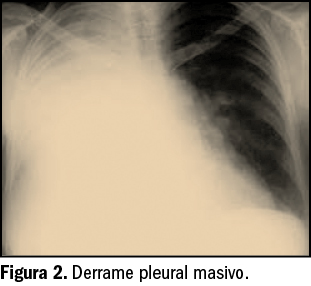

No obstante, algunos expertos apuntan a que la listeriosis es una enfermedad emergente que, por el momento, se considera infradiagnosticada y con importantes lagunas a nivel epidemiológico. Así, un reciente estudio epidemiológico ha analizado los datos –limitados en calidad y cantidad– de hospitalizaciones por listeriosis en España entre 1997 y 2015 (Herrador et al., 2019). En ese periodo, según la base de datos de altas hospitalarias centralizada del Ministerio de Sanidad (Conjunto Mínimo Básico de Datos), se tiene constancia de 5.696 hospitalizaciones con diagnóstico de listeriosis (edad media de los pacientes 58,6 años, 59% hombres). La tasa media fue de 0,67 casos por 100.000 habitantes, con una tendencia creciente en el número de hospitalizaciones durante el período de estudio y con las mayores tasas correspondientes al grupo etario de >65 años, seguido por el grupo de 45 a 64 años (Figura 2).

La distribución geográfica de los casos apunta una concentración mayoritaria en el norte de España, siendo Cataluña, Cantabria y La Rioja las CC.AA. que notificaron las tasas más elevadas de hospitalización por listeriosis, con 23,19, 18,87 y 17,09 casos/100.000 habitantes, respectivamente. La duración media de estancia hospitalaria fue de 21 días y el coste medio de la misma fue superior a 6.300 euros por paciente. Se observó meningoencefalitis y/o septicemia en el 44% (con más frecuencia en varones) y el 8% de los casos. Por su parte, la tasa de mortalidad se situó en 0,06 casos por 100.000 habitantes, representando el 17% de los casos de hospitalización; dos de cada tres muertes se produjeron en pacientes >65 años, con incidencia mayor en los casos de septicemia.